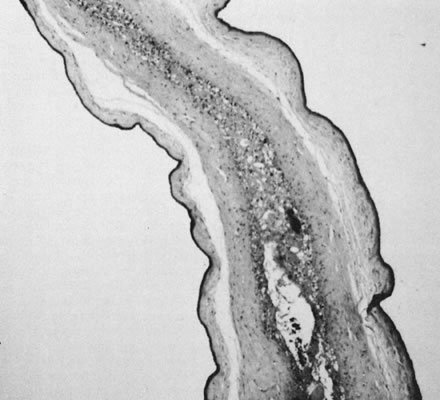

Placenta creta is a generic term for abnormally implantation of placental villi onto (accreta), into (increta), or through (percreta) the uterine myometrium. Placenta percreta may even extend into the bladder. The basic defect is the paucity or absence of decidualized endometrium. Without the normal plane of cleavage at the decidual interface, placental delivery can be difficult, and remnants of the placenta and basal plate can be left in the uterine cavity, with the resultant risks of maternal hemorrhage and infection. Because the lower segment, endocervix, and cornu of the fallopian tube do not transform into decidua, by definition, implantation in these sites results in placenta creta. Placenta creta and placenta previa frequently occur together.60 The most common site of placenta creta is over a previous uterine scar, such as a previous cesarean section, dilatation and curettage, or myomectomy.

Placenta creta is a clinical diagnosis based on difficulty of delivery of the placenta. If the placenta is delivered and examined pathologically, areas of “incompleteness” of the maternal surface can be noted. The range of findings can extend from missing segments of the placenta to focal irregularities of the basal surface. At the edges of incomplete areas, histologic examination may yield smooth muscle (Fig. 10).61,62 This may be the only confirmation of a diagnosis of placenta creta that can be made when only the placenta is submitted to pathology. If a postpartum curettage or hysterectomy specimen is available, the diagnosis is usually confirmed. Histologically, the lesion may be very focal, with absence of decidualized endometrium, and villi implanted directly onto the myometrial smooth muscle (Fig. 11). The invasive trophoblast can be distinguished from endometrial stromal cells by immunohistochemistry; trophoblasts are cytokeratin positive and endometrial cells are vimentin positive. In a set of 462 births at less than 32 weeks' gestation and 108 singleton uncomplicated births at more than 37 weeks' gestation, excluding stillbirth, multiple gestation, chronic hypertension, diabetes mellitus, and fetal congenital anomalies, 44 of 462 (9.5%) of the preterm placentas had basal myometrial fibers versus 0.9% (1/108) of term controls (p < .001). Uteroplacental vessels with abnormal physiologic change were more frequent in cases with myometrial fibers (p < .003), and placental weights were lighter (p < .03). The incidence of basal myofibers was similar in preterm preeclampsia, premature membrane rupture, preterm labor, and nonhypertensive abruption.61 Experimental models suggest that cytotrophoblasts proliferate in response to hypoxia63,64 and may also directly migrate in response to local oxygen tension.65 One response to local hypoxia may be deeper myometrial invasion. Most of the foci of basal myofibers in our data set were found in the immediate vicinity of a uteroplacental vessel with incomplete or absent physiologic conversion. Basal myofibers may indicate local placental hypoperfusion that has prompted local deeper cytotrophoblast invasion.

Fig 11. A. Postpartum hysterectomy specimen. Normal implantation site with invasive trophoblast ( small star ), maternal decidua ( intermediate star ), and myometrium ( large star) (hematoxylin and eosin, ×10). B. Postpartum hysterectomy specimen. Placenta accreta with implantation of villi onto myometrium ( large star ). Few invasive trophoblasts ( small star) and no maternal decidua (hematoxylin and eosin, ×10).